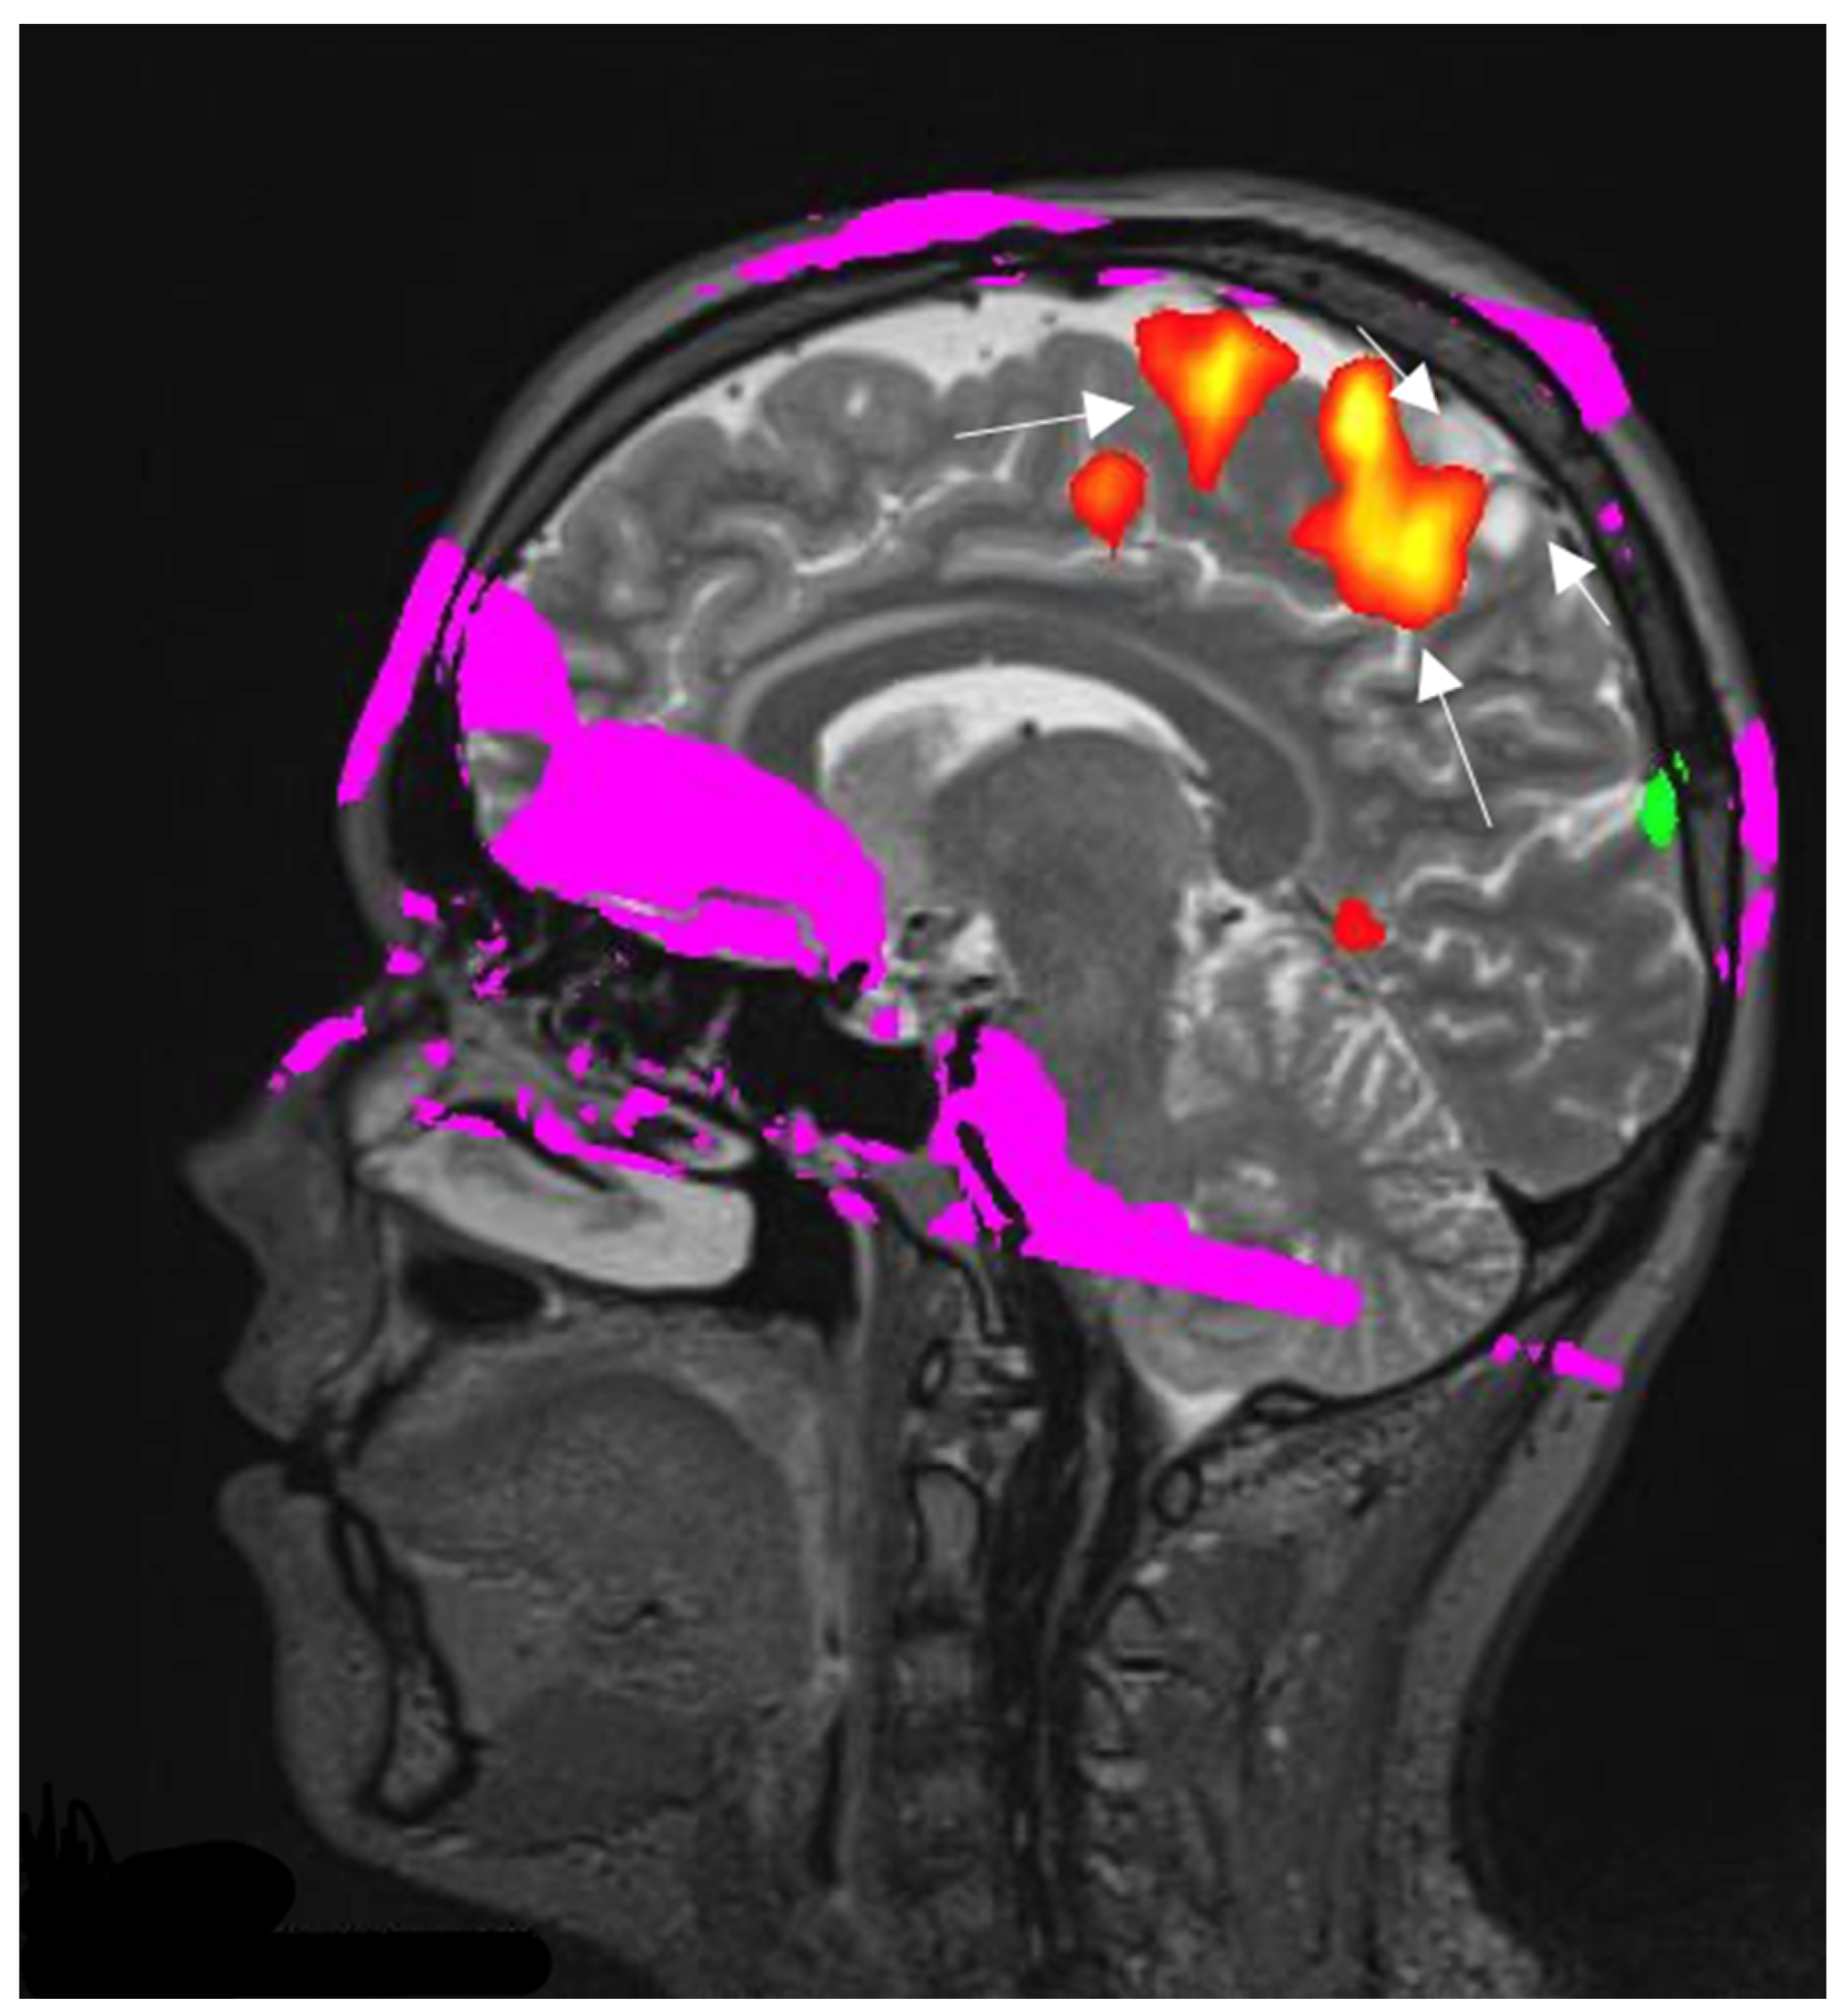

3.4.2. fMRI

- Chamberland, M.; Bernier, M.; Fortin, D.; Whittingstall, K.; Descoteaux, M. 3D interactive tractography-informed resting-state fMRI connectivity. Front. Neurosci. 2015, 9, 275. [Google Scholar] [CrossRef] [PubMed]